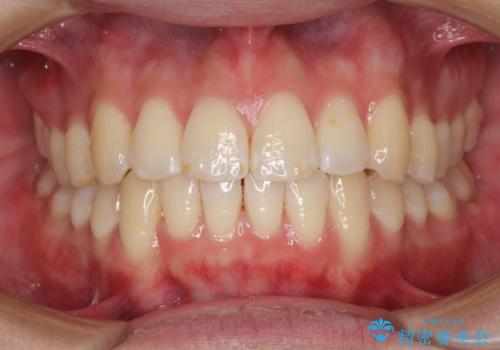

インビザラインで整った口元に

- 前歯のデコボコと若干口元が突出していることを気にして来院された患者様です。

全体的に軽微な叢生が認められ、口元もやや前方に突出していたため、インビザラインでのIPR(歯と歯の間を削る)と歯列全体の後方移動によって歯並びを整えることとしました。

上下ともに歯列の幅が狭かったため、側方に拡大することで前歯のデコボコや突出感を解消するためのスペースを獲得することができました。

歯並びが改善したことはもちろん、咬み合わせの改善まで実感することができ、患者様には大変満足していただけました。